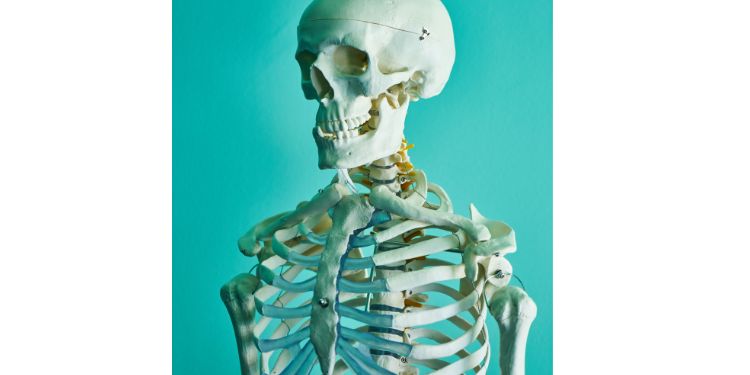

Advancing Skeletal Health Research: The "International Journal of Bone and Mineral Metabolism" is an Open Access, Peer Reviewed Journal committed to advancing knowledge in the multidisciplinary field of skeletal health. IJBM serves as a focal point for researchers, clinicians, and scholars seeking to contribute to the understanding of bone and mineral metabolism.

International Journal of Bone and Mineral Metabolism is dedicated to advancing the understanding of Skeletal Health, Bone Metabolism, Osteoporosis Research, Mineral Homeostasis, Bone Remodeling Dynamics, Orthopedic Disorders, Mineral Homeostasis. IJBM serves as a hub for cutting-edge research, clinical studies, and reviews that contribute to the knowledge base of bone and mineral-related disorders.